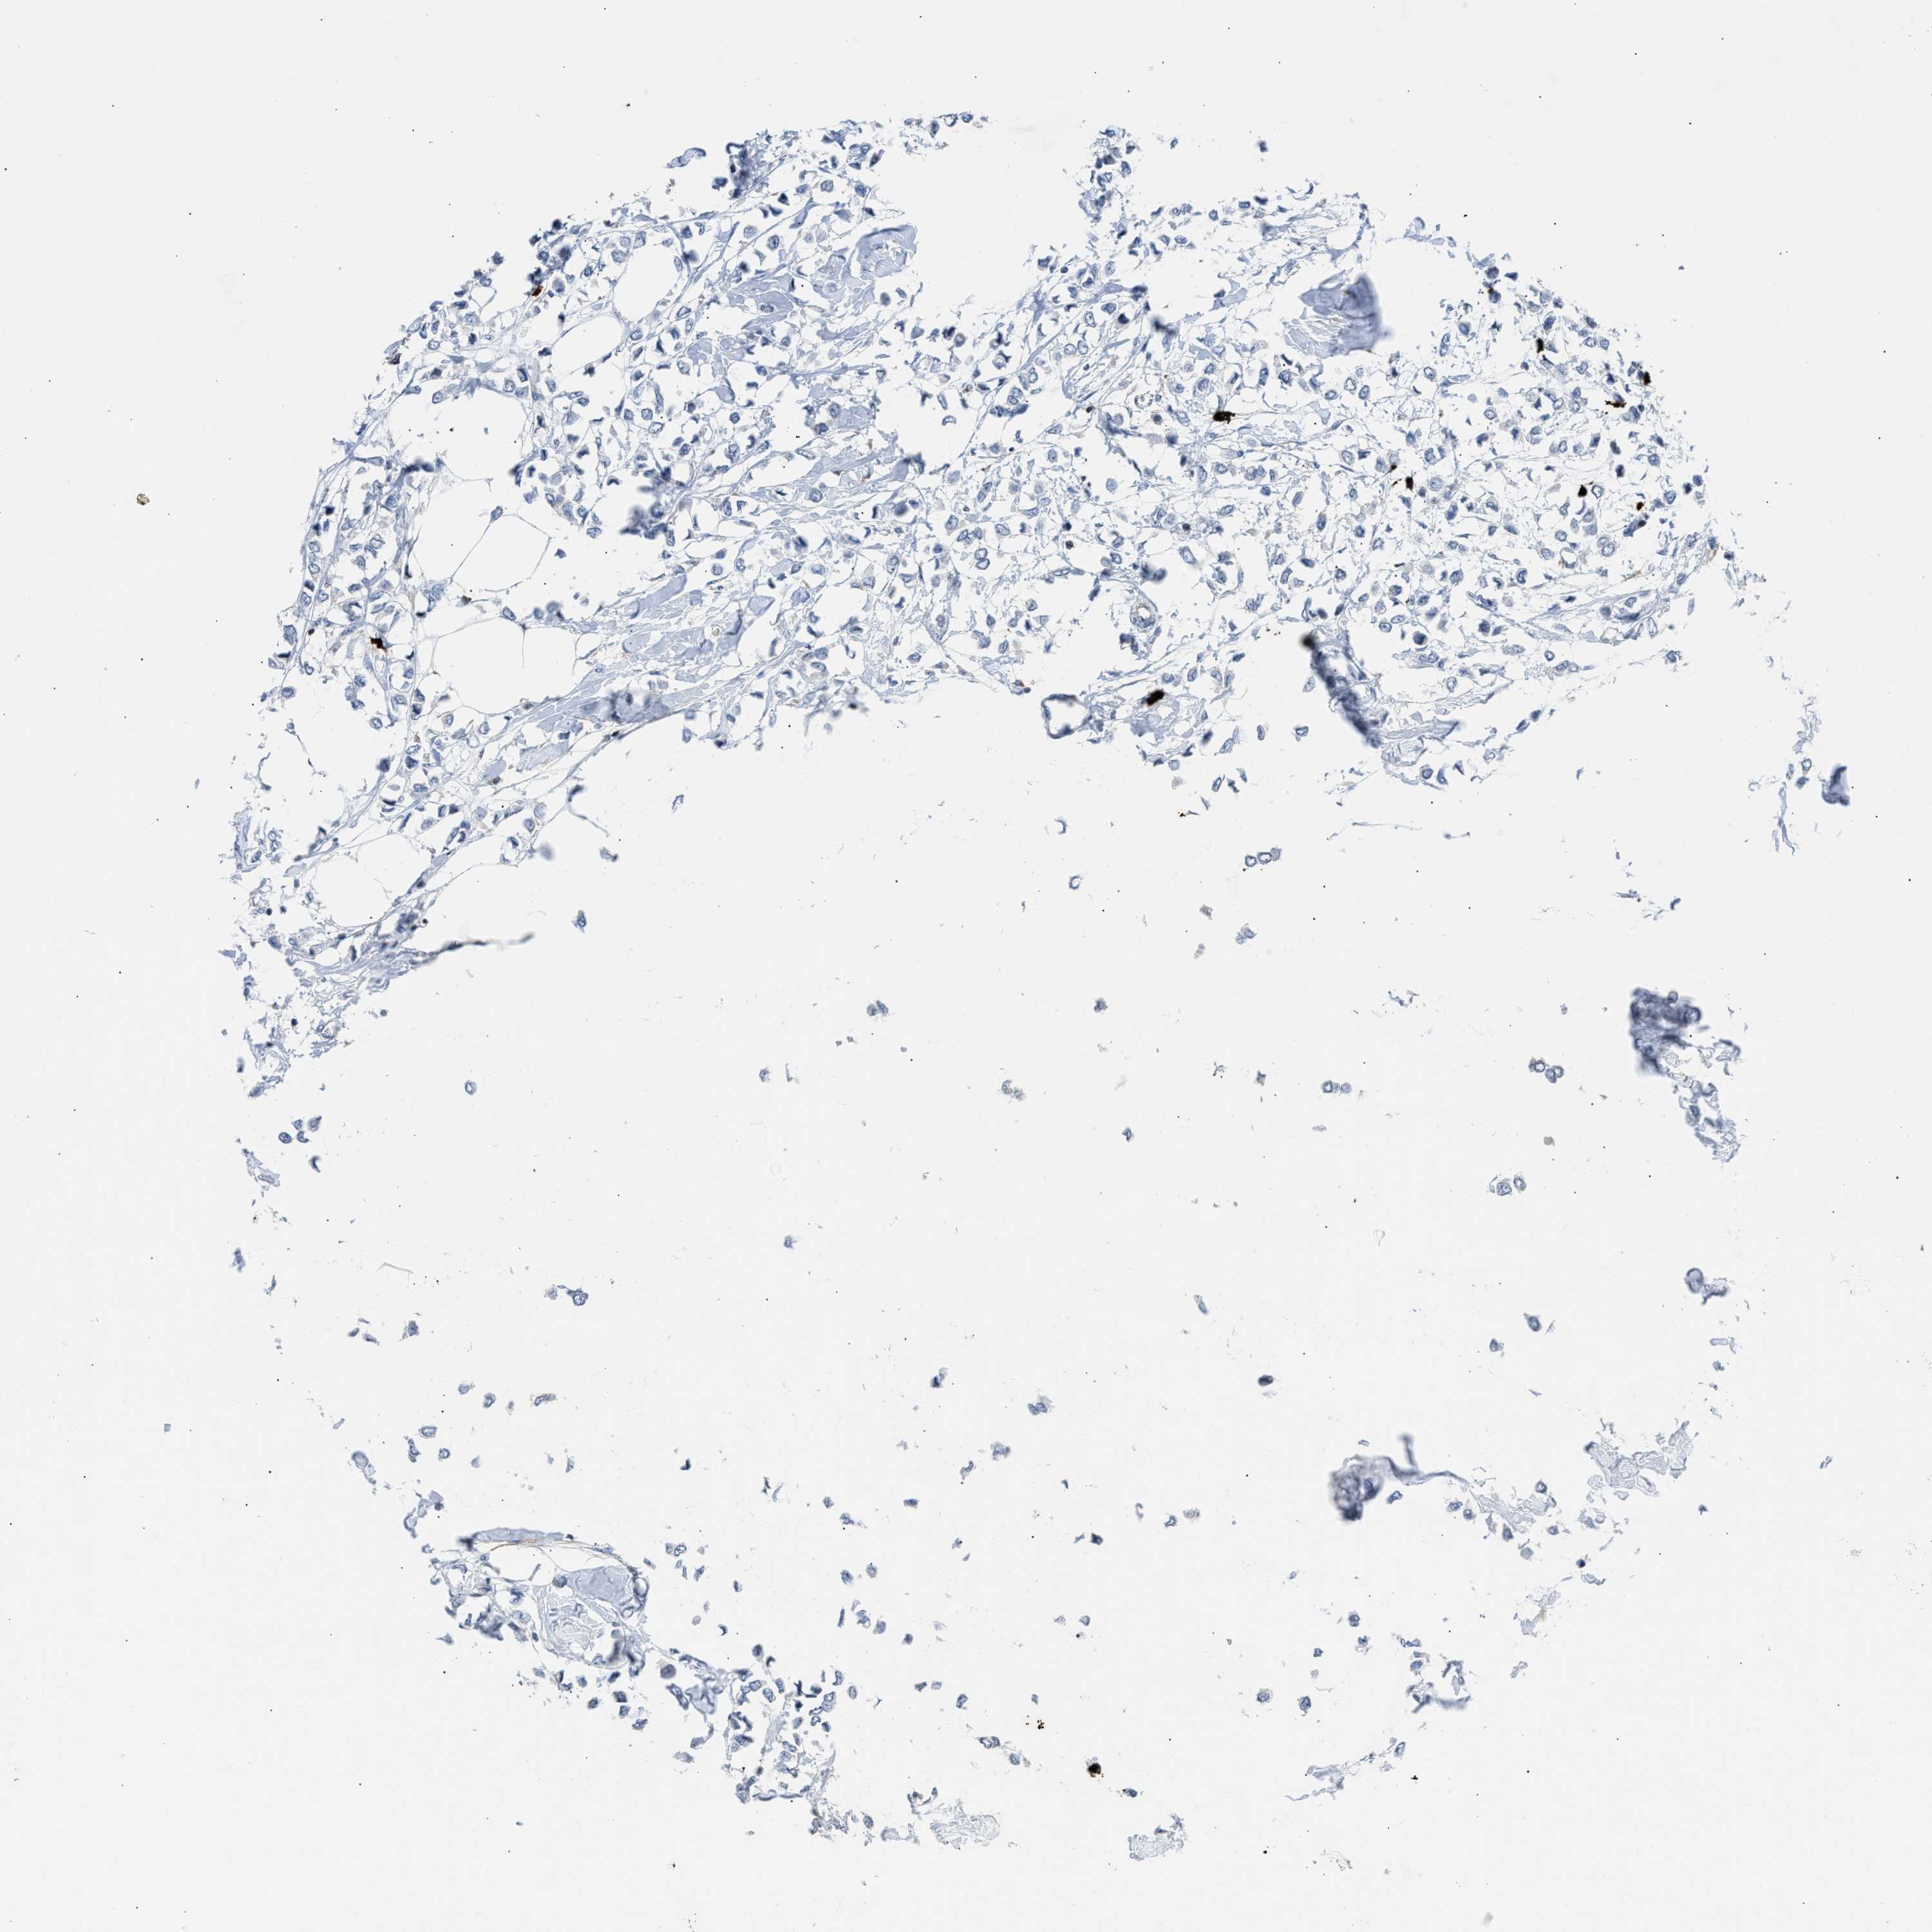

BRCA TCGA BRCA VALIDATION PROTEIN EXPRESSION